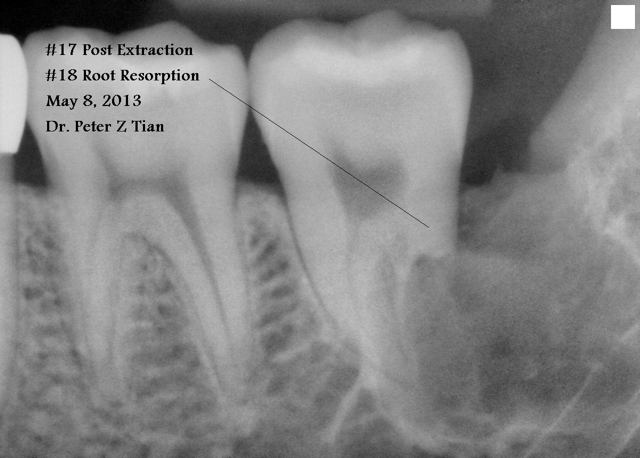

答:要拔,尤其是左右下颌的二个#17 , #32,有可能造成牙体,牙髄,牙周及牙槽骨病变。见附图,我的一病例#17阻生,造成前面#18远中根严重吸收。